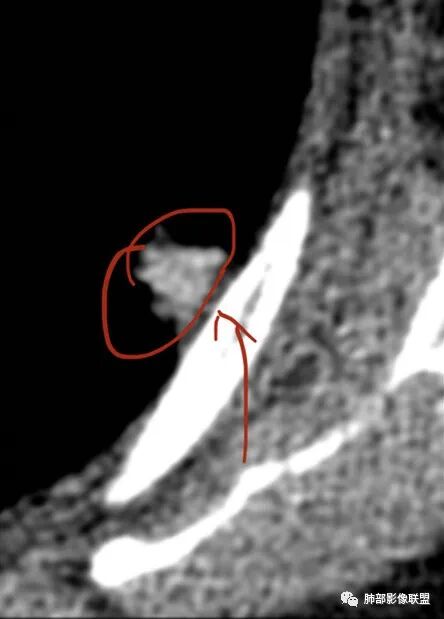

这条血管让我不踏实,像脐凹征吗?

就是这个脐凹征有恶性的特点,所以恶性肯定不能排除

1.脐凹征:分叶状结节局部凹陷的部位受到血管阻力而形成,表现为血管进入分叶之间,脐凹相对比较对称光滑,近肺门侧多见,与血管走行方向一致。

2.95%见于恶性肿瘤,5%为炎性病变。

3.病灶显著强化不支持结核;边界清楚,肺门一侧波浪状改变,患者为老年女性,缺乏临床表现,尽管影像有一些炎性灶特点,但恶性肿瘤性病变不能除外。